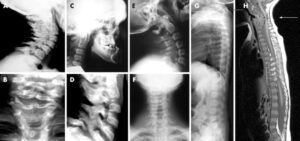

Auf unserer Seite finden Sie umfangreiche Informationen zu orthopädischen Beschwerden und Erkrankungen. Von der Arthrose über Bandscheibenvorfälle bis hin zu Kreuzbandriss und weiteren Sportverletzungen: wir geben Ihnen einen Überblick über die häufigsten orthopädischen Krankheitsbilder, wie sie behandelt werden können und inwieweit ein Bildgebungsverfahren, wie eine (z.B. MRT Knie, Rücken MRT) bei der Diagnose bei der Diagnose unterstützend wirken können.

Viele Betroffene suchen online nach den Ursachen oder Behandlungsmöglichkeiten von Rückenschmerzen, Bänderriss am Fuß oder Bandscheibenvorfall. Einige der orthopädische Beschwerden oder Verletzungen benötigen zu Behandlung eine Bildgebung und Therapie. Alle relevanten Informationen lesen Sie in den jeweiligen Beiträgen.